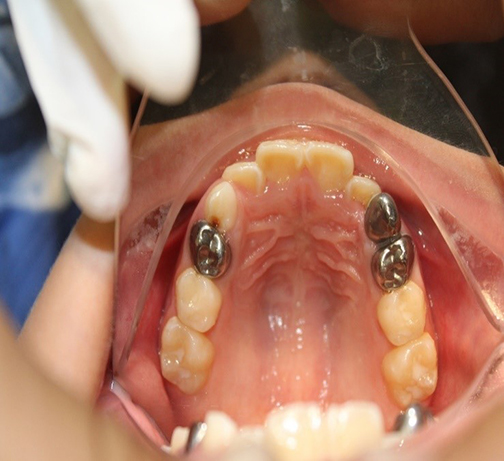

En el examen intraoral se observa dentición mixta temprana en ambas arcadas. Presenta una clase I molar bilateral y clase III canina y una curva de Spee leve, con apiñamiento leve. Presenta una apertura bucal máxima de 51.5 mm

Análisis de Modelos: Se realizó análisis de Moyers y de Pont en los cuales se encuentra una discrepancia entre el espacio disponible y el requerido de - 6 mm y con el análisis de Pont una estrechez transversal en ambos maxilares de - 5 mm.

Alternativa de Tratamiento: Three way. Tornillo tridimensional en la arcada superior para estimular el crecimiento en tres sentidos y 3 minitornillos en el área mandibular con la misma finalidad.

Figura 1.

Figura 2.

Figura 3.

Figura 4.